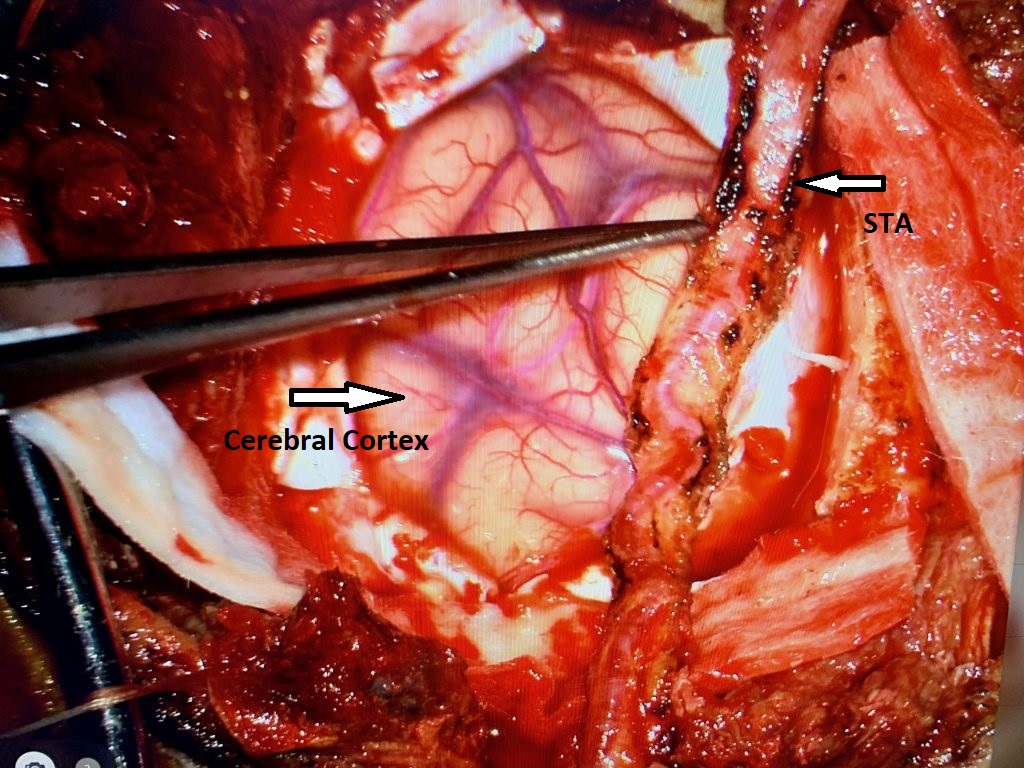

MRI with gadolinium confirmed the likely diagnosis of convexity meningioma, a benign neoplasm of the meninges. Given the location of the tumor, angiography and embolization were […]